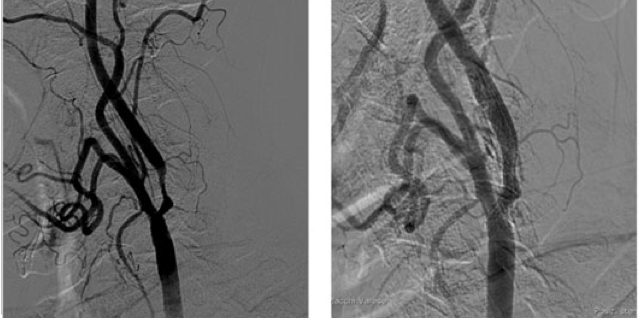

In questo contesto intendiamo degli interventi con un catetere che si possono effettuare attraverso un accesso percutaneo (senza tagli chirurgici) all’interno del vaso sanguigno (trans-luminali). Una possibilità di intervento di questo tipo è l’angioplastica percutanea trans-luminale (PTA), con la quale si può dilatare un vaso sanguigno ristretto, o riaprirlo se occluso, senza operazione. Si esegue mediante un sottile tubo di plastica di 1–2 mm di diametro, munito all’estremità di un palloncino gonfiabile (catetere a palloncino). Con questo palloncino si possono dilatare dall’interno, in modo indolore, tratti ristretti o occlusi delle arterie. Perciò questo procedimento è chiamato anche «dilatazione con il palloncino». Lo si effettua in anestesia locale, senza narcosi. Dato che la posizione esatta del catetere a palloncino dev’essere controllata con un apparecchio radiologico, la PTA si fa nella sala di radiologia.

Se il risultato della dilatazione col palloncino è insufficiente si può procedere all’applicazione di uno stent. Uno stent è un sostegno o un’armatura che mantiene aperta l’arteria dilatata (figura 2) qualora la sola dilatazione col palloncino è insufficiente. Gli stent si possono inserire in quasi tutte le arterie. Si introducono attraverso la stessa apertura praticata sulla cute ed utilizzata per far passare il catetere a palloncino, senza che il paziente se ne accorga.